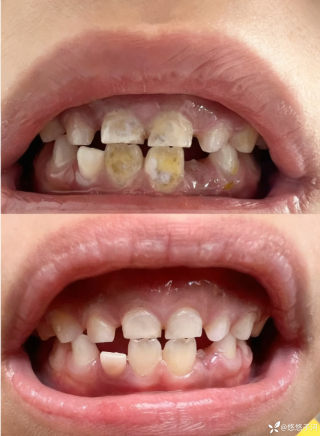

2023年10月26日,来自山东菏泽市成武县的小烨和他家人的命运被彻底改变了。这个原本阳光、可爱的小男孩在一次意外被撞击后,在医院检查出了腹腔内存在肿瘤,并在手术中被切除了包括十二指肠、胰腺、大部分胃和小肠等多个器官。此后便无法再像正常人一样吃饭、喝水,活着要靠长期静脉注射营养液。一份2024年12月由第三方机构出具的司法鉴定意见书显示,当时给小烨做手术的成武县人民医院在该医疗行为中存在过错,与小烨的损害后果之间存在因果关系,建议医疗过错在损害后果中的原因力大小为同等原因。此外,另一份由成武县卫生健康局在2025年9月28日发出的书面答复中显示,成武县人民医院存在24小时内未完成病历;手术知情